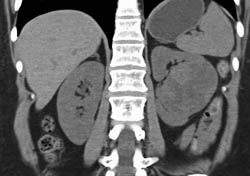

Renal Cell Carcinoma With Renal Vein Extension- See Full Sequence